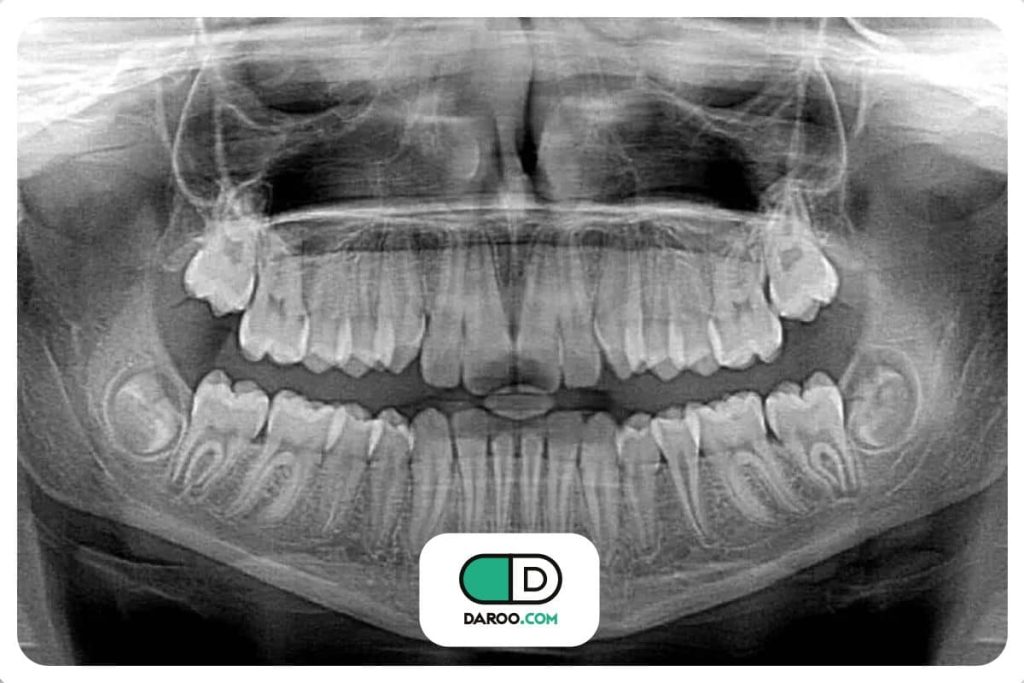

کمترین اشعه، بیشترین دقت؛ دستورالعمل جدید رادیوگرافی دندانپزشکی

به گزارش همشهری آنلاین راهنمای جدید انجمن دندانپزشکی آمریکا (ADA} میگوید عکسبرداری از دندانها فقط در صورت ضرورت بالینی باید تجویز شود تا قرار گرفتن در معرض اشعه برای بیماران و افرادی که در مطب دندانپزشک کار میکنند به حداقل برسد.

این راهنمای جدید همچنین میگوید دندانپزشکان باید قبل از تجویز عکسبرداری با اشعه ایکس، سلامت دهان و دندان فعلی فرد، سن او و هرگونه علائم و نشانههای پوسیدگی دندان یا سایر بیماریها را در نظر بگیرند.